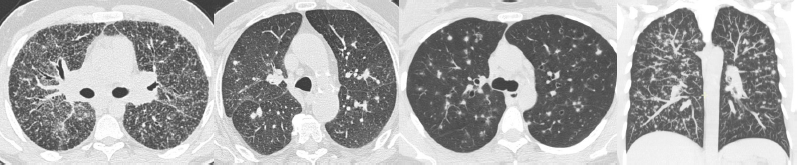

Micronodules